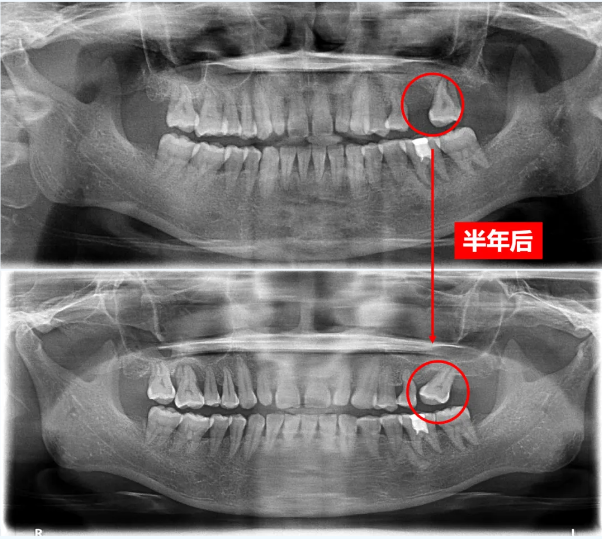

牙周病,被称为「口腔中的白蚁」,它潜伏深处,缓慢却持续地吞噬支撑牙齿的骨组织:

●早期: 牙龈红肿、刷牙出血;

●中期: 牙龈退缩、牙缝变大、出现口臭;

●晚期: 牙槽骨吸收、牙齿松动乃至脱落。

牙周组织如同地基,牙齿则是高楼,根基一旦松动,再精致的外观也难以久立。一旦出现异常症状,务必尽早就医干预,避免「慢病养大病」。